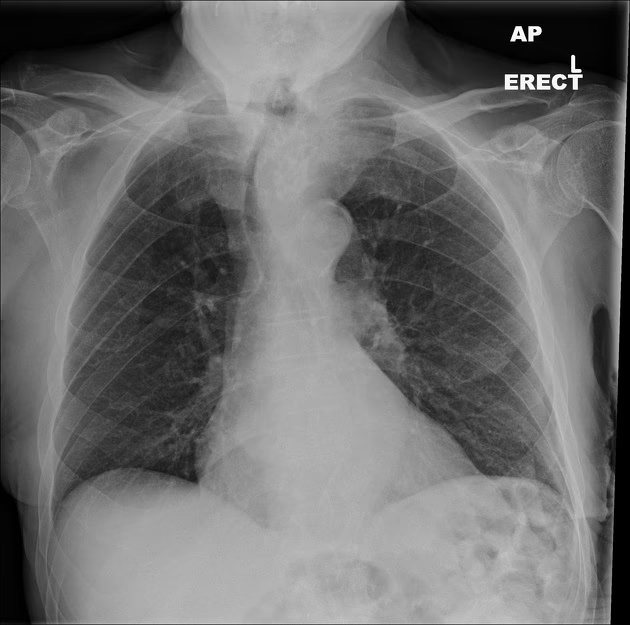

Røntgen af Brystkassen (Thoraxrøntgen)

En røntgenundersøgelse af brystkassen er en simpel billeddannelsestest, der giver et billede af hjertet, lungerne og de omkringliggende strukturer. Selvom den er mindre detaljeret end en ekkokardiografi, er den et vigtigt værktøj, især i mere fremskredne stadier af sygdommen. Hos patienter med hypertyreose-induceret kardiomyopati kan et røntgenbillede afsløre:

- Kardiomegali (forstørret hjerte): Skyggen, som hjertet kaster på røntgenbilledet, vil være større end normalt. Dette sker, fordi hjertemusklen har arbejdet hårdere over en længere periode, hvilket fører til fortykkelse (hypertrofi) og senere udvidelse (dilatation). Skyggen er ofte symmetrisk og trekantet med basen opad mod halsen.

- Lungekongestion (væske i lungerne): Hvis hjertet ikke pumper effektivt, kan blod og væske hobe sig op i lungerne. På et røntgenbillede ses dette som tågede eller slørede områder, hvilket indikerer, at hjertesvigt er under udvikling.

- Forskydning af luftrøret (trachea): I tilfælde, hvor skjoldbruskkirtlen er markant forstørret og strækker sig ned i brystkassen (substernal struma), kan røntgenbilledet vise, at luftrøret er skubbet til siden eller indsnævret.

Disse fund på et røntgenbillede af brystkassen er stærke indikatorer på, at hjertet er alvorligt påvirket af hypertyreosen, og at der er behov for omgående behandling.

| Røntgen af Brystkassen | Hjertets størrelse, form og tegn på væske i lungerne | Forstørret hjerteskygge (kardiomegali), tegn på væske i lungerne (lungeødem) |

Hvorfor viser et røntgenbillede af brystkassen et forstørret hjerte?

Den konstante overstimulering fra forhøjede skjoldbruskkirtelhormoner tvinger hjertemusklen til at arbejde hårdere og hurtigere. Over tid tilpasser musklen sig denne øgede belastning ved at blive tykkere og større (hypertrofi), ligesom enhver anden muskel, der trænes hårdt. Dette fører til sidst til en udvidelse (dilatation) af hjertekamrene, hvilket ses som en forstørret hjerteskygge på et røntgenbillede.